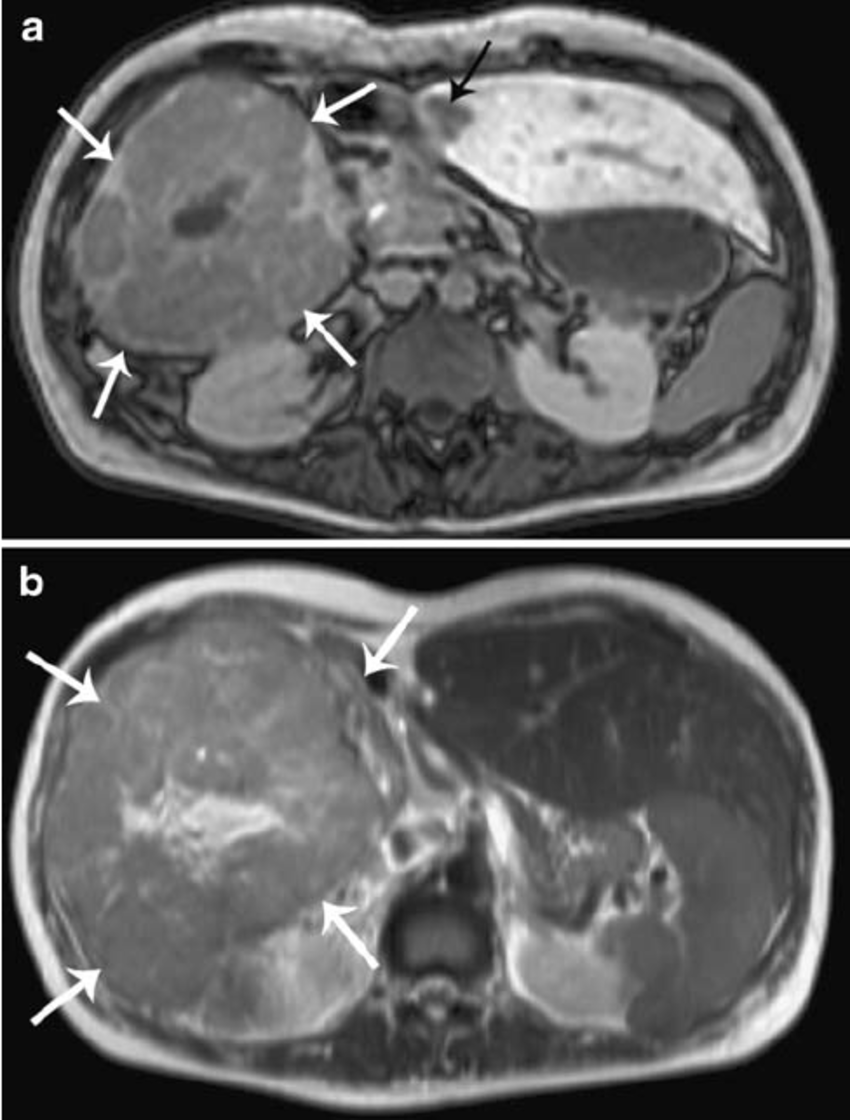

hemangioma: mais comum, hiperproliferação vascular

us com lesão homogêna e hipoecóica

tc: enchimento precoce da perifeira padrão centripeto wash-in (globuliforme). Na fase tardia, lesão hiperintensa (no adenoma é hipodensa)

T1: hipointenso

T2: hiperintenso em relação ao parênquima hepático, mas menos intenso que o liquor

T1 com gadolíneo: realce periférico nodular descontínuo que progride de forma centrípeta nas imagens tardias